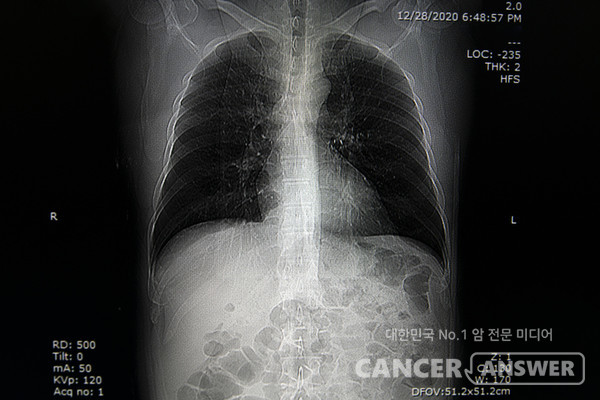

폐에서 '간유리 결절'이 보인다는 소견을 받고난 후 암이 아닐까 걱정하는 이들이 많다. 간유리 결절은 폐 꽈리에 부위에 유리를 갈아서 뿌려놓은 듯 뿌옇게 음영이 보이는 상태를 말한다.

간유리 결절은 폐에 생긴 염증으로 인해 굳어지는 섬유화 현상으로 생긴다. 내부가 흐리고 뿌연 게 특징이다. 폐에 음영은 증가했지만 폐혈관이나 기관지 등 조직이 정상적으로 보이는 경우가 많다. 반면 고형 결절은 폐혈관이나 기관지 같은 조직이 보이지 않을 정도로 음영이 증가하고 진한 특징이 있다.